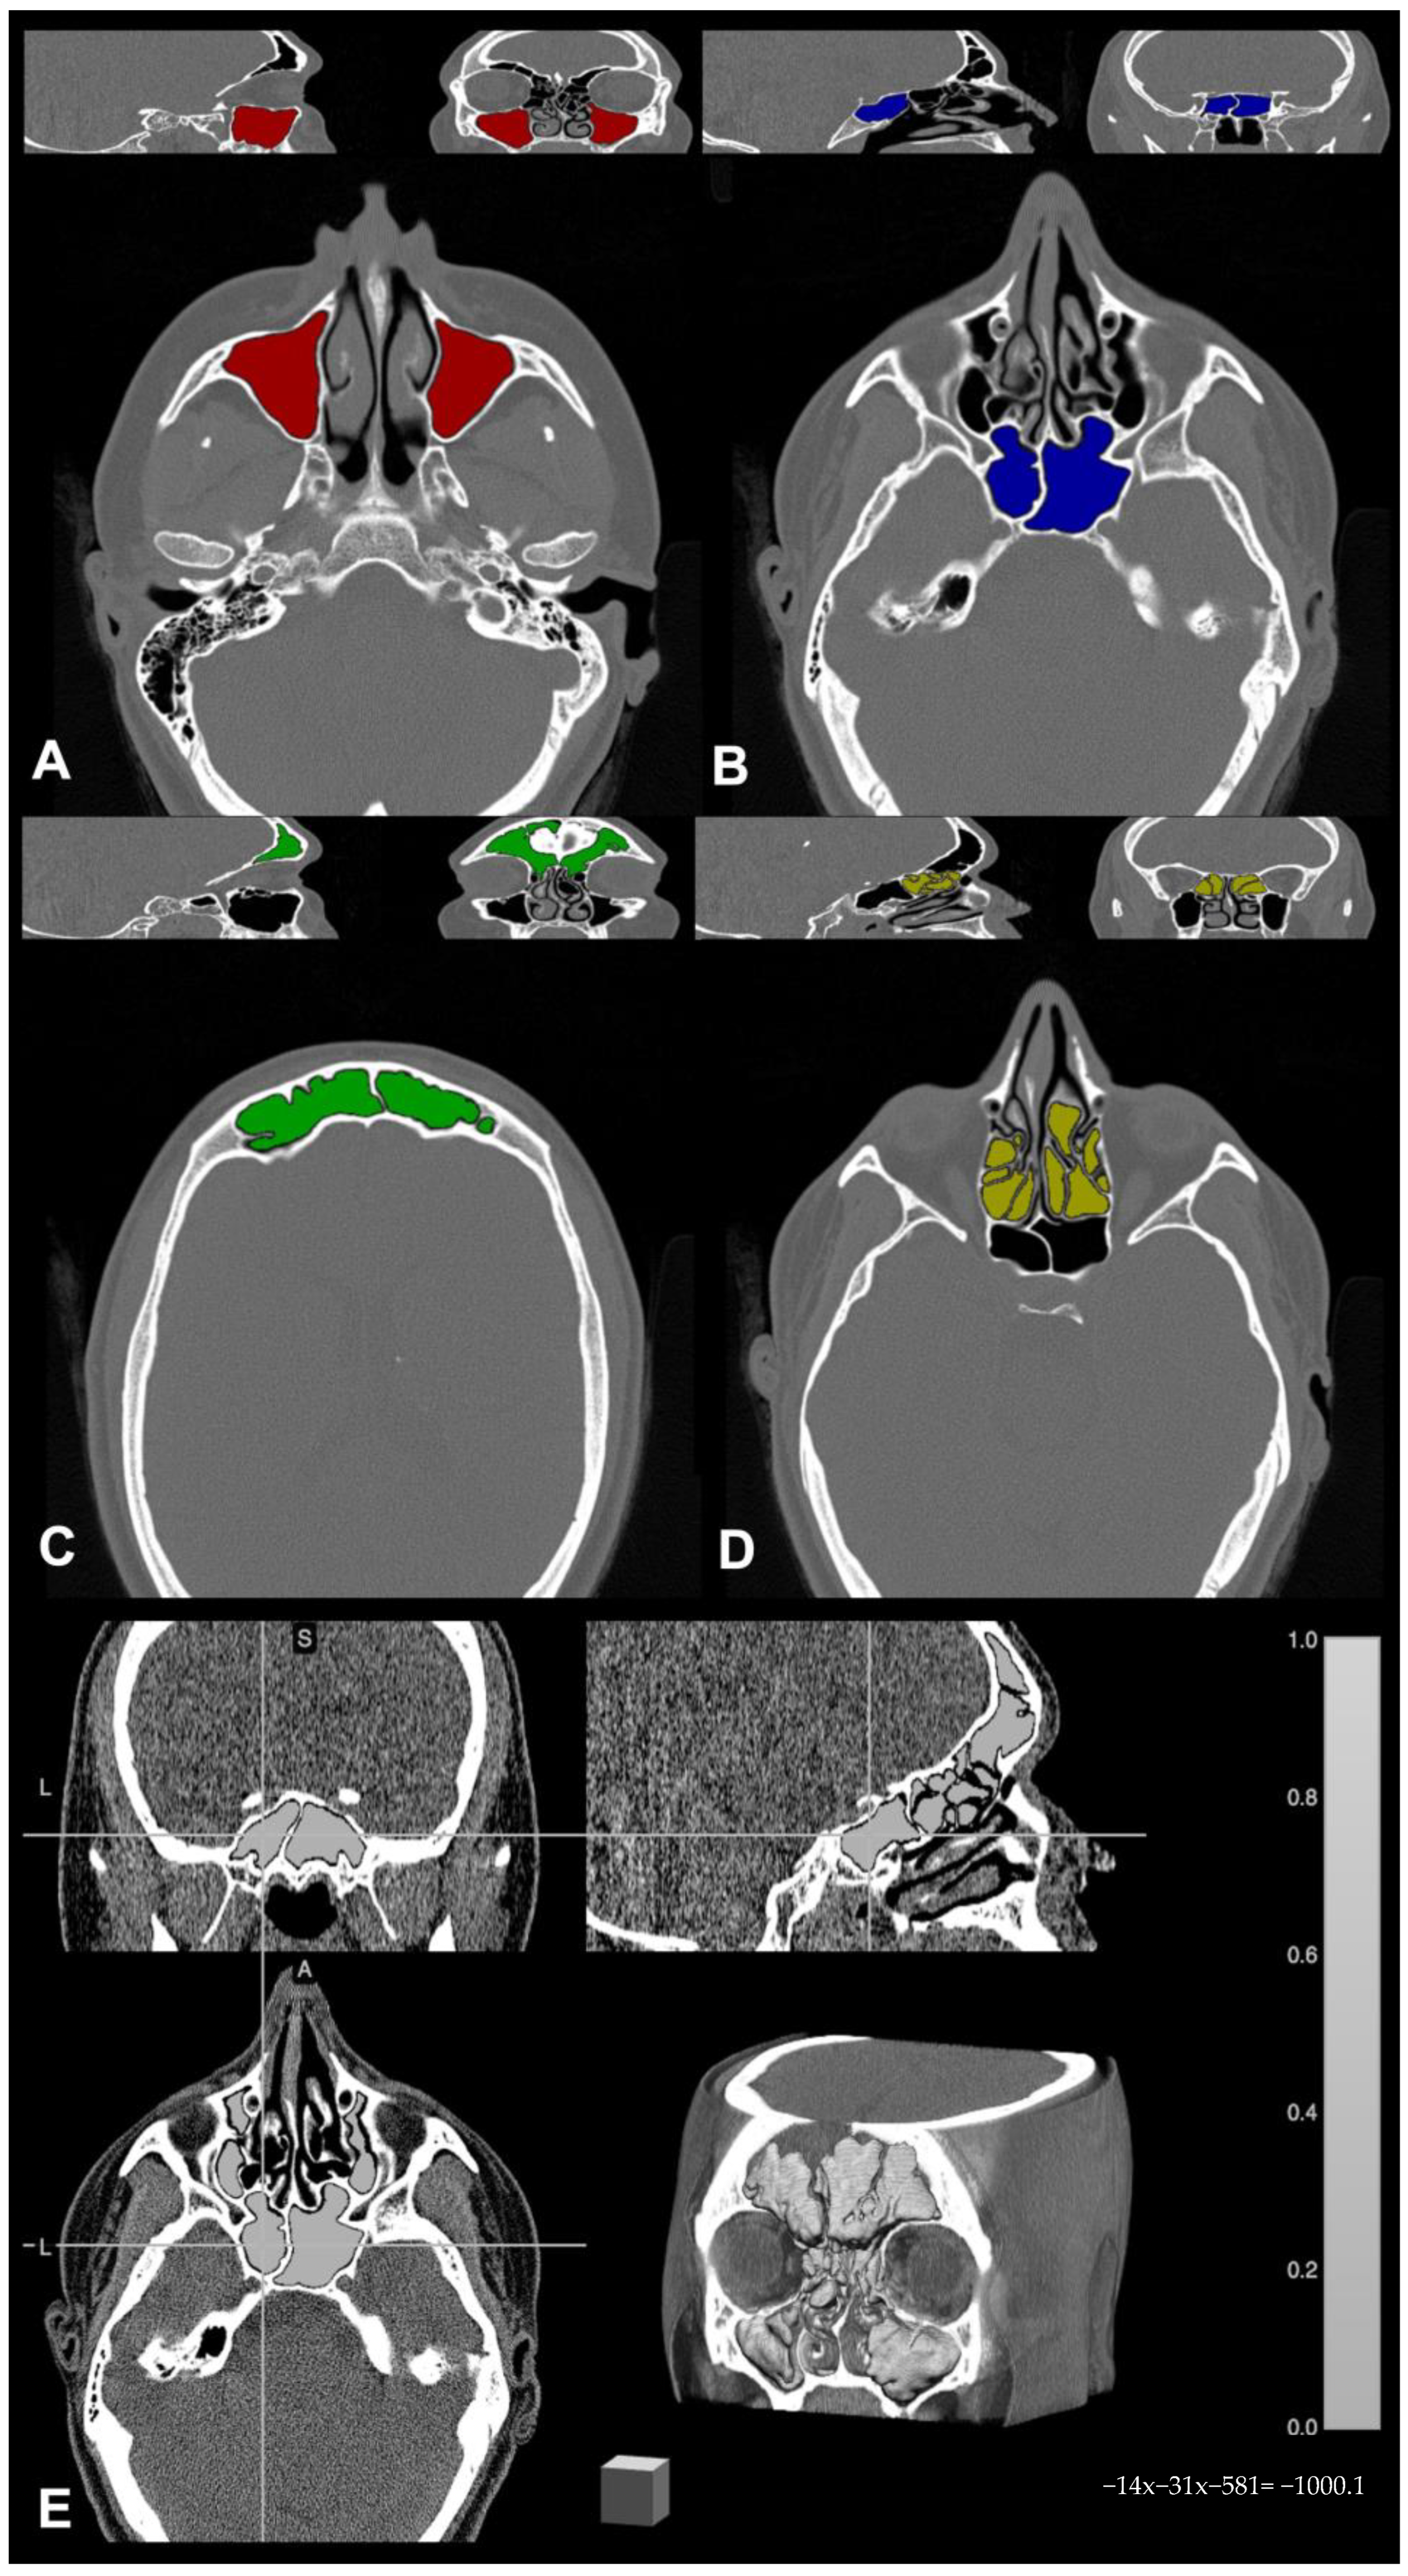

Paranasal sinus CT scans were stored and anonymized, then converted from DICOM to NIfTI format by using the free online tool dcm2niix (https://www.nitrc.org/plugins/mwiki/index.php/dcm2nii:MainPage, (accessed on 15 March 2020)). For each CT examination, paranasal sinuses were individually segmented by an experienced neuroradiologist, and masks were drawn on each scan using the freely available software MRIcron 2019 (https://www.nitrc.org/projects/mricron (accessed on 15 March 2020)). In detail, bony landmarks were identified to delineate the sinus on the axial CT scan slice that contained one or more cavities, and the area inside such boundaries was filled automatically using the specific tool in the same software; these manually segmented sinus cavities constituted the region of interest (ROI) binary masks for each sinus. In case of mucosal thickening or sinus occlusion, binary masks of occupancy in the ROIs were also generated with the same procedure, and ROI masks were subsequently combined with the occupancy masks to remove any boundary inconsistencies [26]. Once completed, sinus masks were independently saved in the volume of interest (VOI) file format, and these VOI masks were used for calculating the computational volumes; namely, the output concerning each sinus was saved in a report of volumetric descriptive data for further statistical analysis. An example of segmentation showing the four sinus volume masks superimposed to the relative native CT examination is shown in Figure 1.

Figure 1.

Example of paranasal sinus segmentation by means of MRIcron 2019 software (available at nitrc.org): (A) maxillary sinus (red); (B) sphenoid sinus (blue); (C) frontal sinus (green); (D) ethmoid sinus (yellow); (E) overall paranasal sinuses segmentation with three orthogonal plans and 3D reconstruction (light gray).